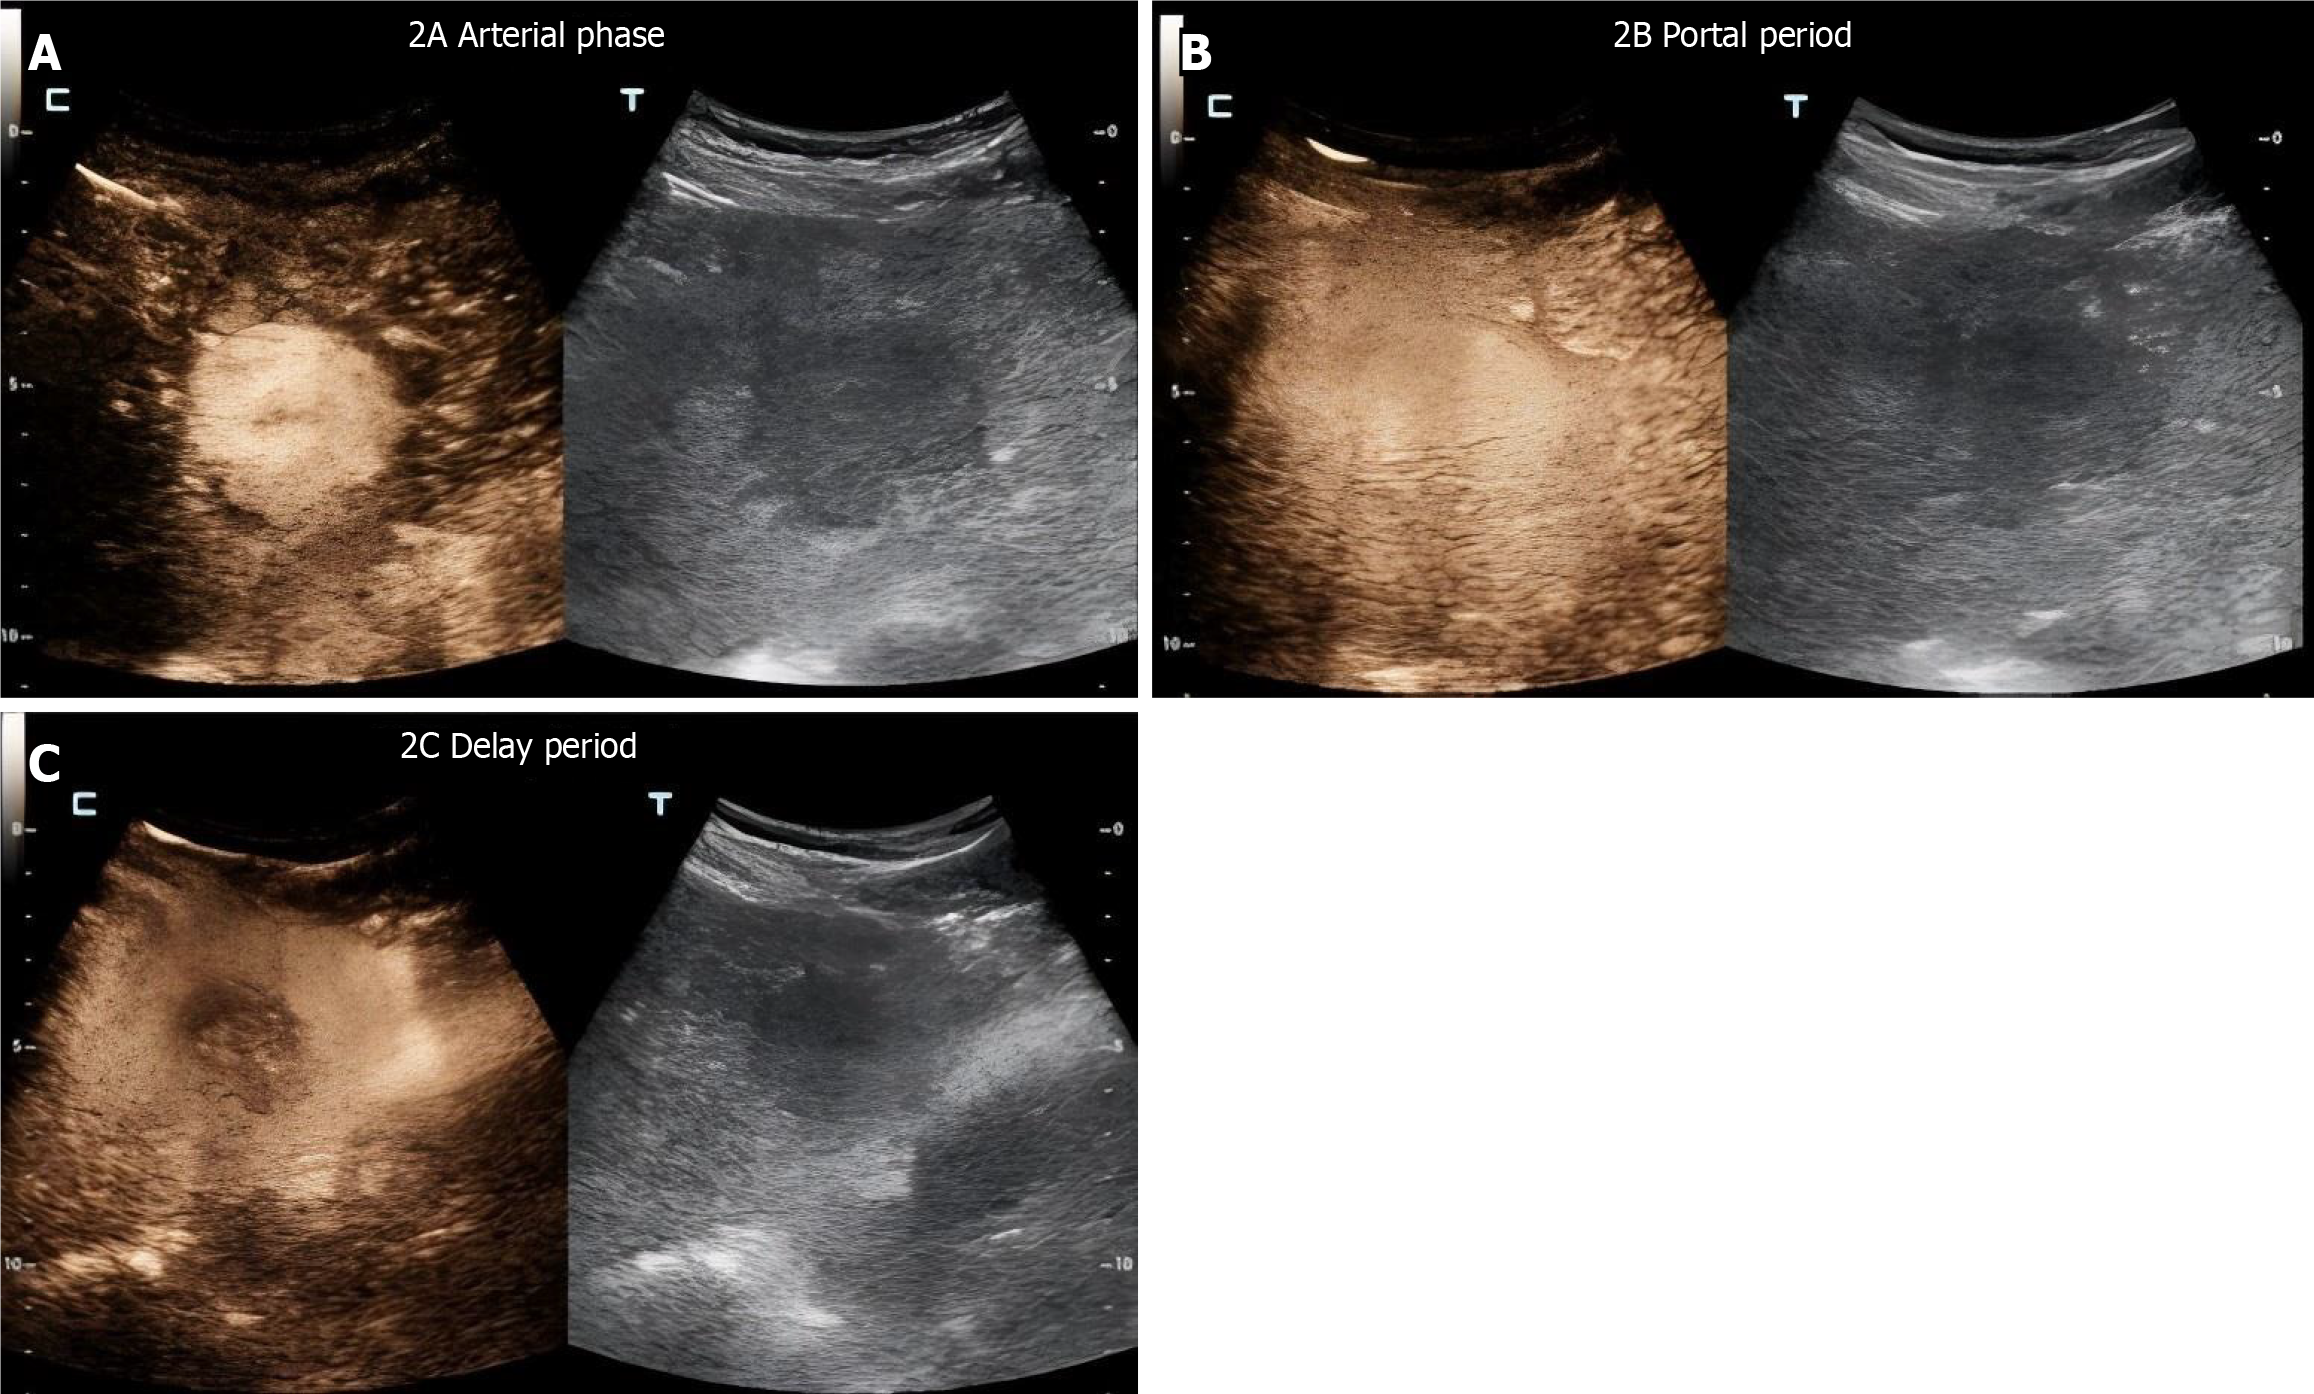

Figure 2 Edge detection of a lesion in a typical case.

A: Results of arterial phase detection. No significant abnormal enhancement is observed inside the hematoma or at the edge of the capsule during the arterial phase, and arterial bleeding is reduced after embolization; B: Results of portal phase detection, where the contrast agent enters the venous system through capillaries from the arteries, reflecting tissue gaps and microvascular permeability; C: Results of the delayed detection period, during which the contrast agent should gradually clear and abnormal enhancement indicates continuous bleeding or vascular leakage.